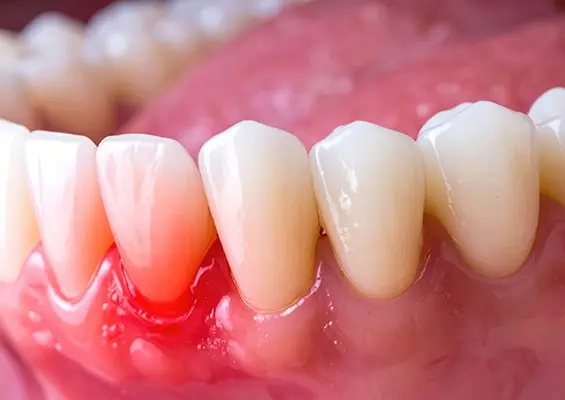

Na podstawie badania klinicznego oraz badań obrazowych stwierdzono znaczne zniszczenie twardych tkanek zębów oraz zmiany w okolicy okołowierzchołkowej zębów 36, 37, zajęcie furkacji zęba 37 oraz obecność zatrzymanego zęba 38.